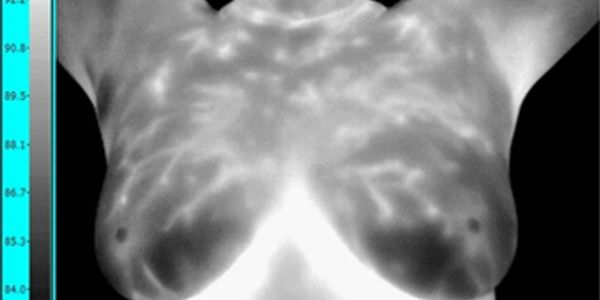

For all women beginning at age 20. Thermal imaging, combined with a clinical breast exam are two of the most powerful tools in the risk assessment of breast disease. Breast thermal imaging has no dangerous radiation, is 100% safe, painless, and affordable.

Breast infrared thermal imaging is a cornerstone to detecting breast disease at its earliest stages. When combined with mammography and a clinical breast exam - your chances of detecting breast disease is substantially increased.